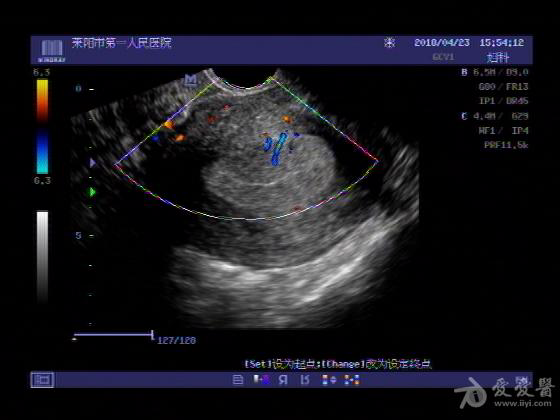

女,48岁,月经量多,两个月,一年前出现过类似现象,刮宫吃药后缓解。

超声可见:子宫内膜显著增厚,后肌壁内膜可见范围约3.27X0.90CM低回声区,CDFI显示较丰富线样血流,宫底宫腔内见类**状低回声结节。前肌壁见多发类圆形低回声结节。

超声提示:子宫内膜增厚(建议刮宫病理),子宫多发肌瘤

病理结果:内膜增生